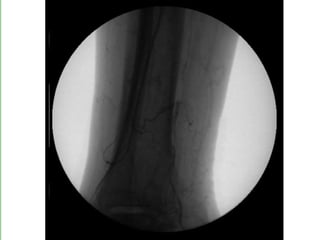

ISQUÉMIA CRÍTICA TRATAMENTO - Revascularização Cirurgia convencional Cirurgia endovascular - Proximal - Distal - Multisegmentar

ISQUÉMIA CRÍTICA TRATAMENTO- Revascularização Cirurgia convencional Cirurgia endovascular - Proximal - Distal - Multisegmentar